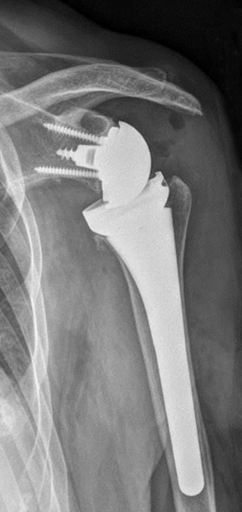

When conservative measures are no longer providing adequate pain relief, a surgical options may be explored. Depending on the overall functional health of your shoulder, your surgeon may recommend a total or reverse total shoulder. A total shoulder is often suggested when there is osteoarthritis in the shoulder and all of the tendons that make up the rotator cuff are intact and functioning properly. The rotator cuff provides added stability to the shoulder joint. When you do not have an intact and functioning rotator cuff, a reverse total shoulder may be recommended. This type of replacement is designed to provide the positional stability that your shoulder needs to have pain-free movement.